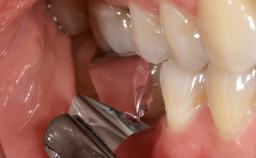

A 79-year-old female patient was referred to the Department of Periodontology of the University of Bern, Switzerland by her private dentist in May 2019. She had been rehabilitated in May 2005 with two tissue-level implants (Institut Straumann AG, Basel Switzerland) at sites 13 and 15, supporting a three-unit cemented fixed dental prosthesis (FDP). The metal-ceramic FDP had been cemented permanently with a glass-ionomer cement (Ketac Cem; 3M ESPE, Seefeld, Germany). Implant 13 had been diagnosed with peri-implant mucositis by the referring dentist in the course of regular supportive therapy. The patient was in good general health, did not smoke, and exhibited good self-performed plaque control.